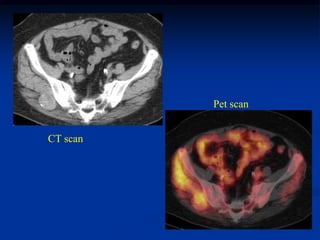

Case #1198.3            CT scan 4/06

09

Sag T-1        Gad

Axial T-1 upper   T-2 upper

T-2 lower         Cor STIR